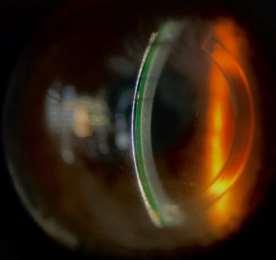

Figura4.Perfildeadaptacióndellentehíbridoenojoizquierdo,tomadaconOCT-ASMS39Syrius.

Laevaluaciónbiomicroscópicadellentemostróuna adecuada alineacióncorneoconjuntival sinapoyo en la unión, con bóveda central de 45µm, pericentral de 60µm y prelimbal de 150-107 µm); su asentamiento sobre la superficie ocular fue evaluado en los intervalos de cinco (5) y veinte (20) minutos posteriores a la inserción del lente, y tan sólo al retirarlo se percibió una inusual adherencia que obligó a ajustar el ángulo de la faldilla por uno menos plano.

Figura6Imagenbiomicroscópicacentraldellentehíbrido,indicandoconflechaverde,launiónentreelLCRGPyelhidrofílico(Hyperbond),enun ojotranquilo.